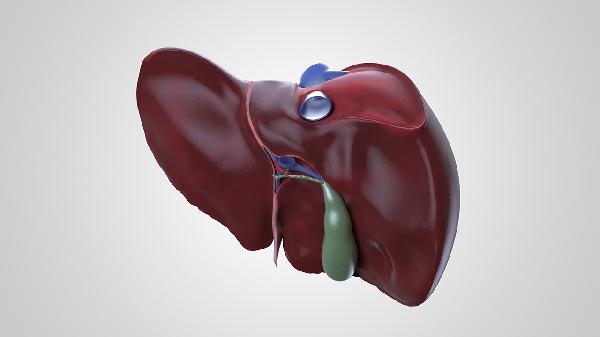

肝脏穿刺通常会有轻微疼痛感,但多数患者可以耐受。肝脏穿刺主要用于诊断肝脏疾病,如肝炎、肝硬化或肝脏肿瘤等。